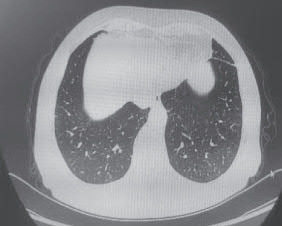

(4)胸部影像变化。

2022-12-16 胸部CT(图2-6-3):双肺散在间质性炎症,考虑特殊感染可能。

图2-6-3 2022-12-16 胸部CT